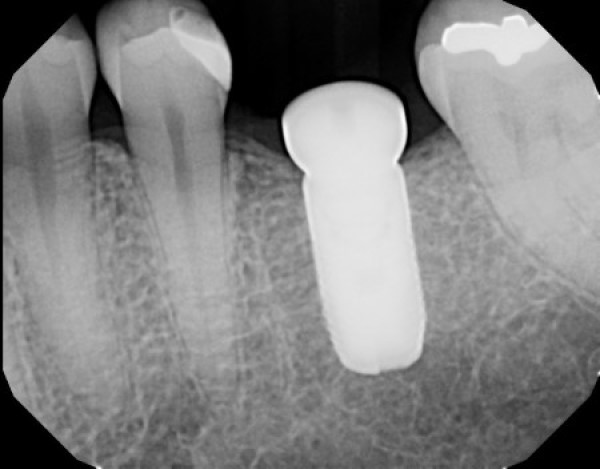

Our technology has actually been FDA-cleared and successfully regenerating maxillofacial bone for years across the country.

Developed by the pioneers at SteinerBio, this innovative regenerative material transforms weak, poorly mineralized bone into healthy vital bone.